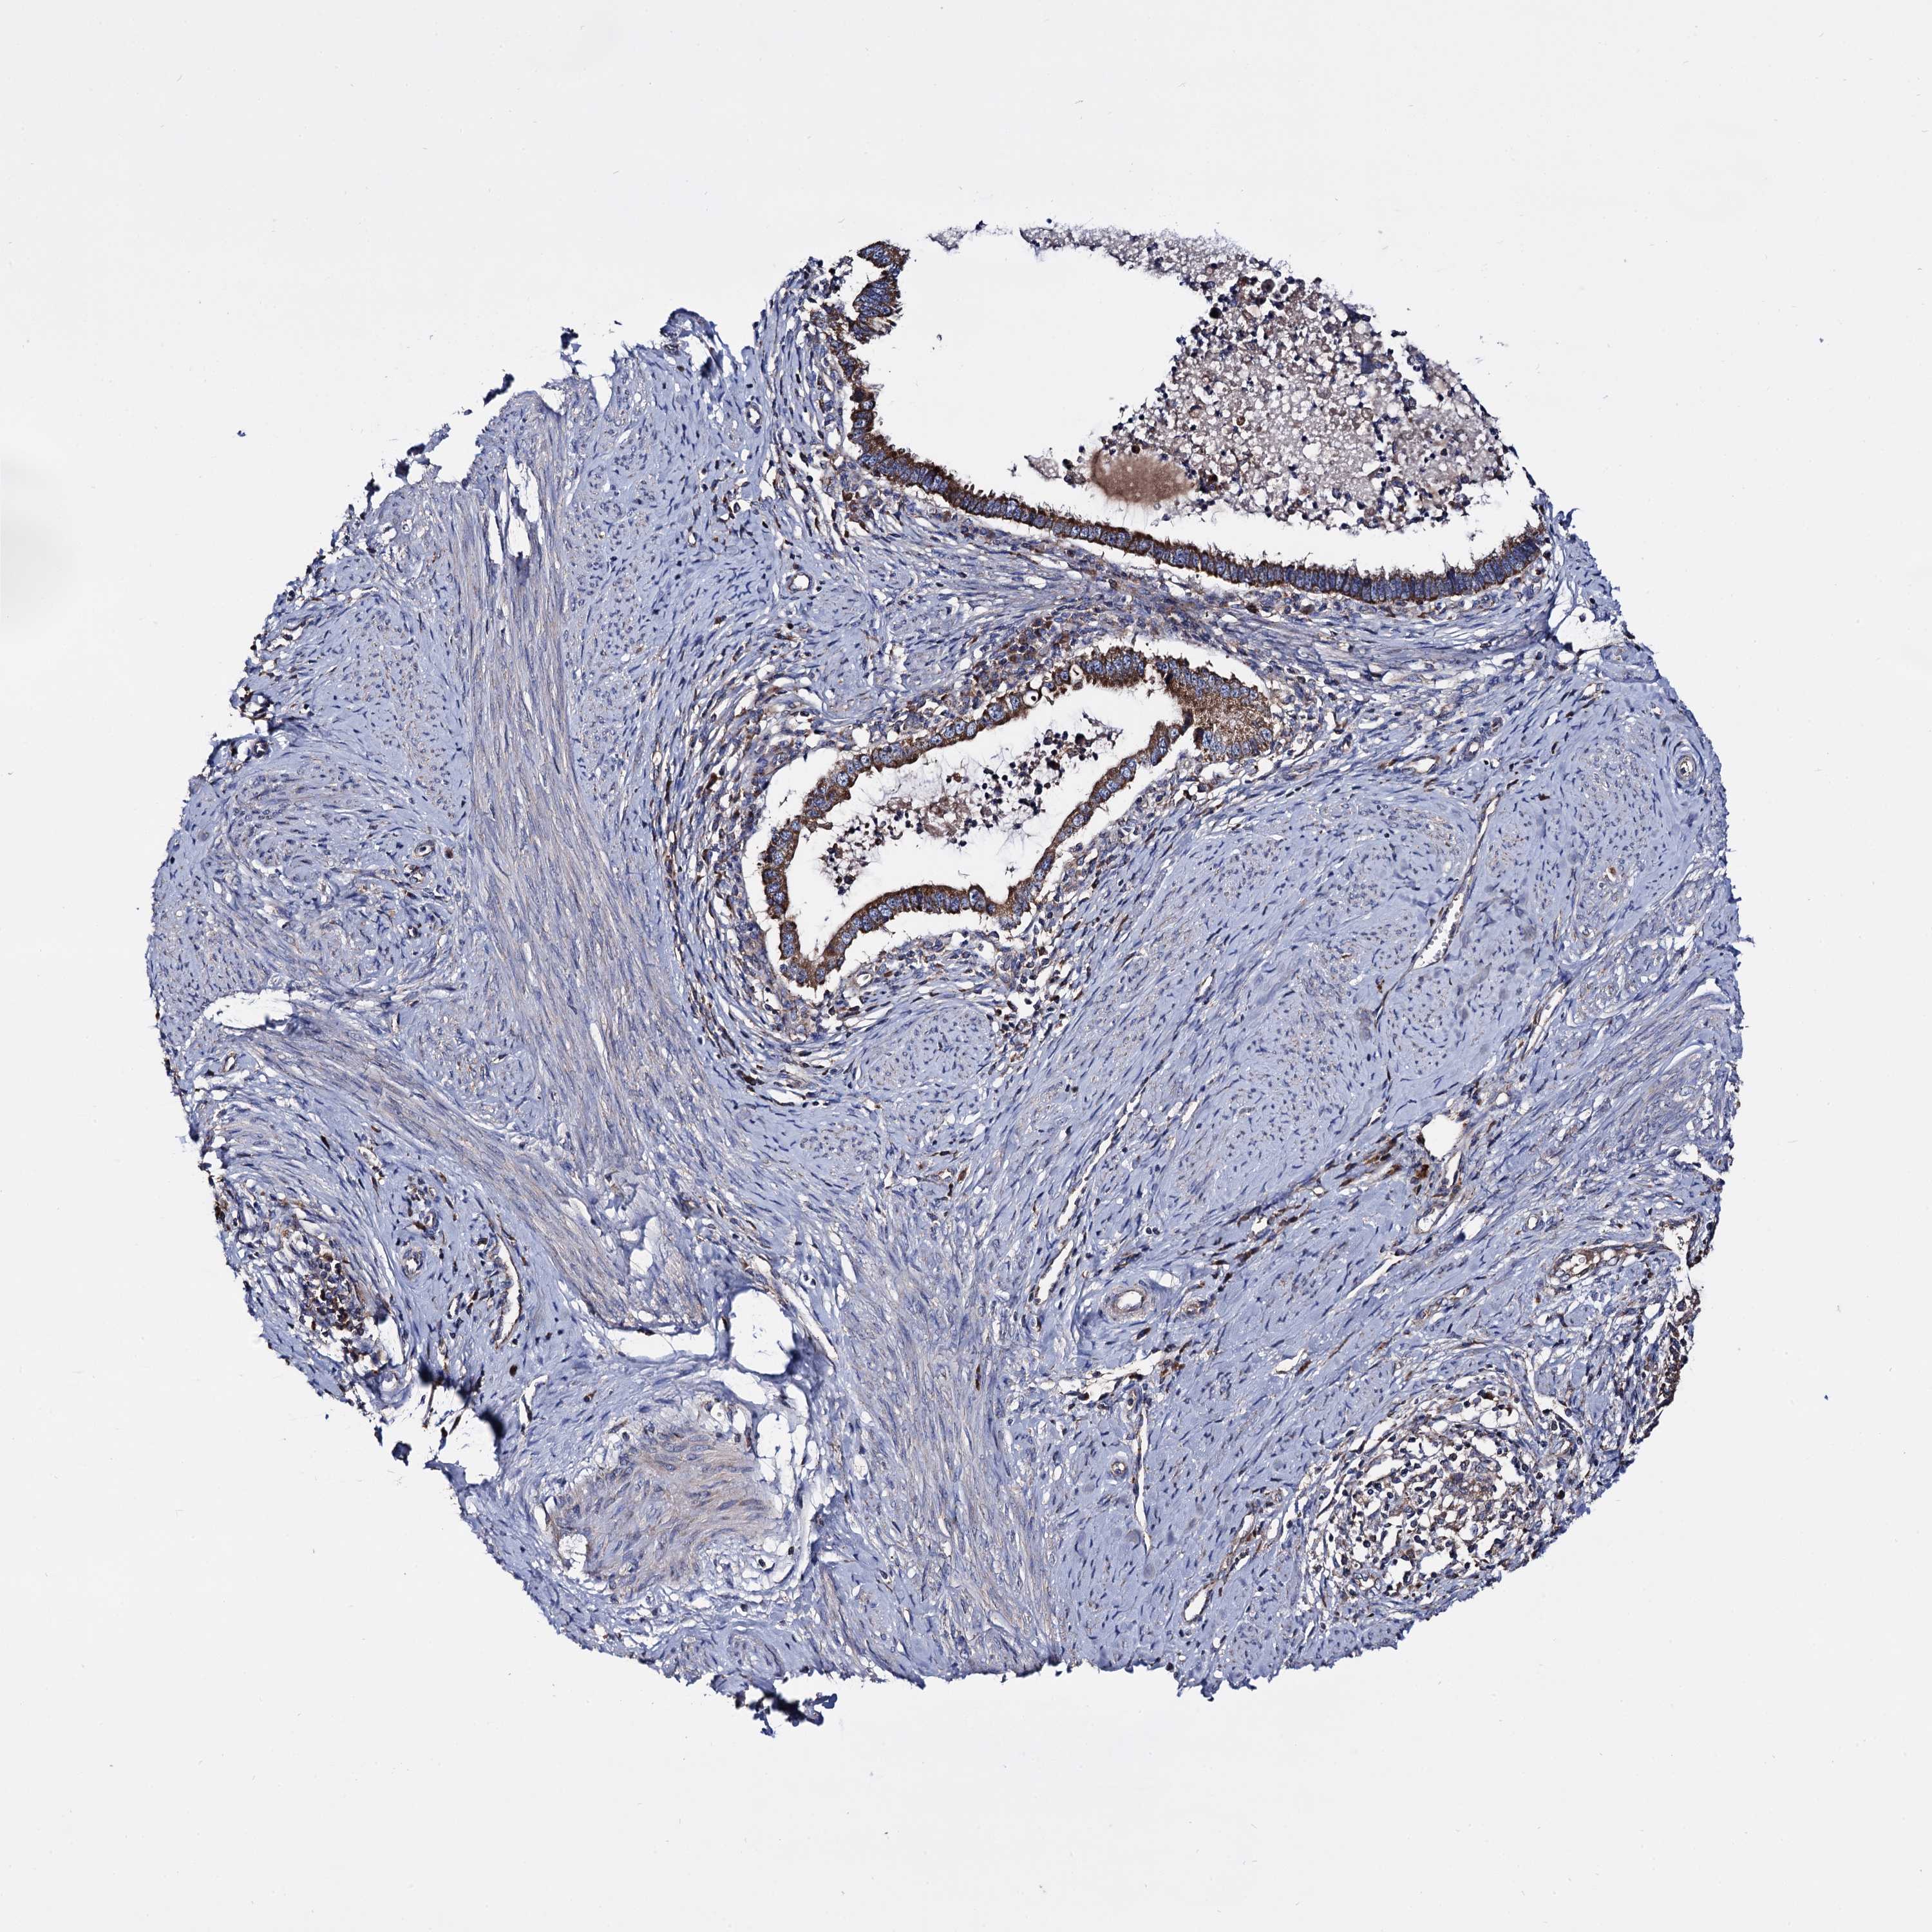

CERVICAL CANCER - Protein expressioni

A mouse-over function shows sample information and annotation data. Click on an image to view it in a full screen mode. Samples can be filtered based on level of antibody staining by selecting one or several of the following categories: high, medium, low and not detected. The assay and annotation is described here.

Note that samples used for immunohistochemistry by the Human Protein Atlas do not correspond to samples in the TCGA dataset.

Antibody stainingi

Antibody staining in the annotated cell types in the current human tissue is reported as not detected, low, medium, or high, based on conventional immunohistochemistry profiling in selected tissues. This score is based on the combination of the staining intensity and fraction of stained cells.

Each image is clickable and will lead to virtual microscopy that enables deeper exploration of all samples and also displays staining intensity scores, fraction scores and subcellular localization as well as patient and tissue information for each sample.

Antibody HPA040845

Staining

High

Medium

Low

Not detected

Intensity

Strong

Moderate

Weak

Negative

Quantity

>75%

75%-25%

<25%

None

Location

Nuclear

Cytoplasmic/membranous

Cytoplasmic/membranous,nuclear

Squamous cell carcinoma, NOS

Adenocarcinoma, NOS